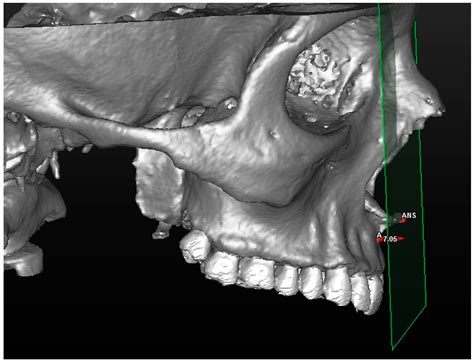

In diagnostic imaging, the Anterior Nasal Spine is a valuable landmark for interpreting radiographs and CT scans. Its consistent position and density make it easily identifiable on imaging studies, aiding in the diagnosis and treatment planning of various conditions. For example, in cases of nasal trauma, the Anterior Nasal Spine can help in assessing the extent of the injury and planning the appropriate surgical intervention.

Additionally, the Anterior Nasal Spine is used as a reference point in cephalometric analysis, a technique used in orthodontics to assess the skeletal and dental relationships of the craniofacial complex. This analysis helps in planning orthodontic treatments and predicting treatment outcomes.

• Advanced Imaging Techniques: Utilizing advanced imaging techniques, such as 3D imaging and virtual reality, to study the Anterior Nasal Spine in greater detail. These techniques can provide a more comprehensive understanding of its anatomy and clinical relevance.